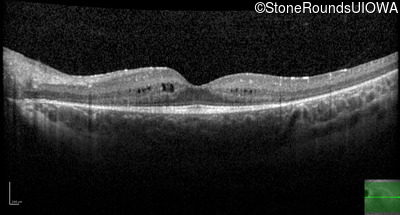

Age at visit: 10 years